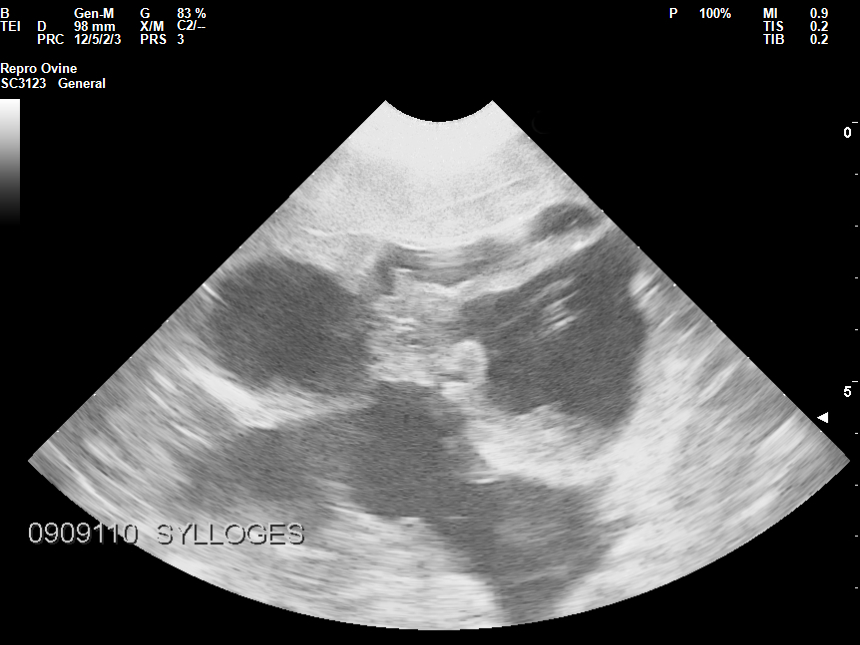

ΥΠΕΡΗΧΟΤΟΜΟΓΡΑΦΙΑ: ΓΡΗΓΟΡΗ, ΑΝΩΔΥΝΗ, ΑΚΙΝΔΥΝΗ ΚΑΙ ΧΑΜΗΛΟΥ ΚΟΣΤΟΥΣ ΕΞΕΤΑΣΗ

Η υπερηχοτομογραφία αποτελεί βασική μέθοδο διαγνωστικής απεικόνισης της εσωτερικής δομής ενός (εν ζωή) ζώου, που βασίζεται στην αξιοποίηση των υπερηχητικών κυμάτων. Είναι μία μη-επεμβατική μέθοδος χωρίς παρενέργειες, δεν χρησιμοποιεί ηλεκτρομαγνητική ακτινοβολία κάτι που τη καθιστά ασφαλή ακόμη και στα μικρά ζώα. Έχει καλή διακριτική ικανότητα και δημιουργεί εικόνες υψηλής ανάλυσης, σε πραγματικό χρόνο. Πραγματοποιείται από εξειδικευμένο κτηνίατρο - υπερηχολόγο, κυρίως στις παραγωγικές κτηνοτροφικές μονάδες για την διάγνωση της εγκυμοσύνης, έτσι ώστε να γίνει σωστά ο διαχωρισμός των ζώων σε έγκυα ή μη και να επιλεχθεί το κατάλληλο εμβολιακό πρόγραμμα.

• Διάγνωση εγκυμοσύνης

• Διάγνωση πολυδυμίας

• Διάγνωση παθολογικών καταστάσεων μήτρας